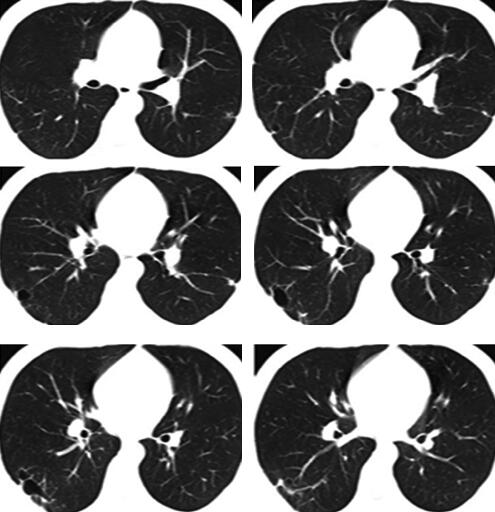

4天后热退,复查血常规白细胞计数及中性粒细胞百分比均恢复正常,治疗似乎有效,但此时患者出现咳铁锈色痰,偶有新鲜血痰,2013年2月27日复查胸部CT示右下叶后基底段原斑片影吸收,但背段有新发小片状阴影,带有小空洞,外基底段病灶也出现多发小空洞(图2),此时本该引起警觉却被“体温下来是硬道理”给冲昏了头脑,关键症状咯血也想当然的用肺炎解释了,治疗上联合左氧氟沙星氯化钠静脉滴注以加强抗感染治疗,2013年3月5日复查胸部CT(图3)可见右肺下叶背段病灶较前缩小,而外基底段斑片状渗出影较前明显吸收,更让医生坚定了肺炎的诊断。但此时的病人仍有气短(仅活动时)和轻度胸痛,咯血有加重倾向,最多一次量约5ml,呈鲜红色,这时医生感到困惑了。

图2

图3

停用华法林观察1周,咯血和气短症状逐渐缓解,2013年4月14日复查胸部CT与2013年4月5日相比较,新发的磨玻璃影全部吸收,进一步证实为肺泡积血导致;而左肺下叶沿支气管走行斑片影、粟粒影与2013年4月5日比较明显吸收,原右下叶空洞较前进一步缩小(图7)。结合患者临床表现和影像学特征,考虑咯血原因为华法林药物副作用和(或)肺栓塞导致肺梗死所致,故改为低分子肝素皮下注射抗凝治疗。后咯血逐渐减少,出院后继续规律低分子肝素治疗。2013年5月22日患者门诊随访,无咯血,无气短,无胸痛,无发热,复查胸部CT示右下肺空洞基本吸收,遗留两个薄壁的小空腔及少许条索影(图8)。考虑患者为青年学生,久坐习惯可去除,规范低分子肝素皮下注射抗凝治疗总疗程3个月后停止抗凝。2013年10月16日复查CTPA提示未见肺动脉充盈缺损。

图7

图8